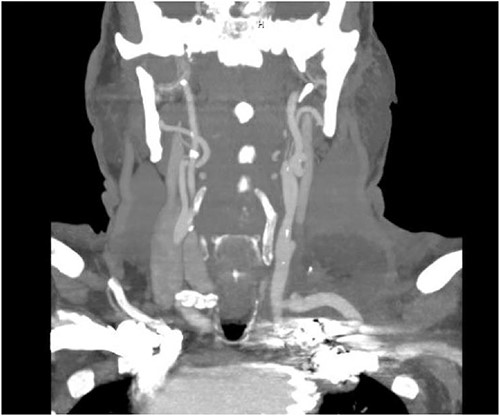

The patient is a 70-year-old male with an incidental finding of a proximal LSA aneurysm on computed tomography (CT) angiography of the chest performed for shortness of breath. He had no dysphagia, neurologic or vascular occlusive symptoms. He had no history of trauma or known congenital anomaly. The aneurysm had a maximal diameter of 3.4 cm and was located at the origin of the artery (Fig. 1). An aberrant left vertebral artery and hypoplastic right vertebral artery were also identified. The left vertebral artery originated from the aortic arch proximal to the LSA takeoff (Fig. 2) and provided dominant posterior cerebral circulation.

Preoperative CTA demonstrating LSA aneurysm; located at the origin from the aortic arch.